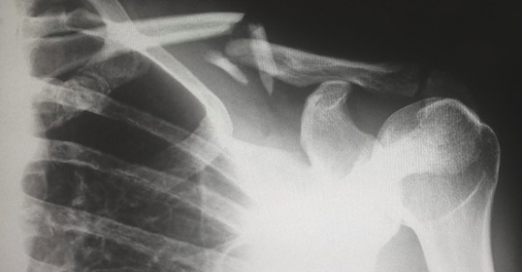

Les médecins ont ensuite effectué un scanner et ont remarqué que la tige s’était repositionnée d’une façon ou d’une autre dans la moitié inférieure du poumon gauche de la femme.

Les médecins pensent que l’implant aurait pu être placé trop profondément dans le bras de la femme, ce qui l’aurait fait entrer dans sa circulation sanguine et l’a fait voyager dans son corps.